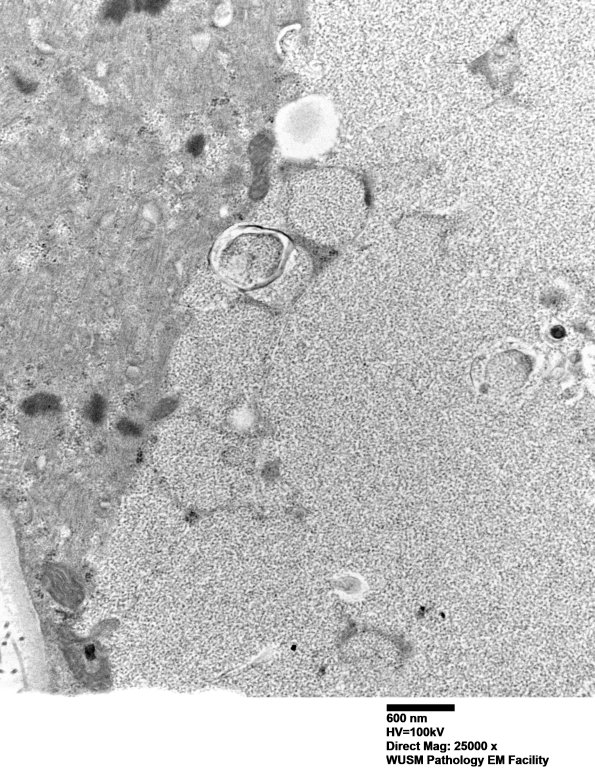

This atrophic fiber shows little residual of its sarcomeric substructure. (electron micrographs)